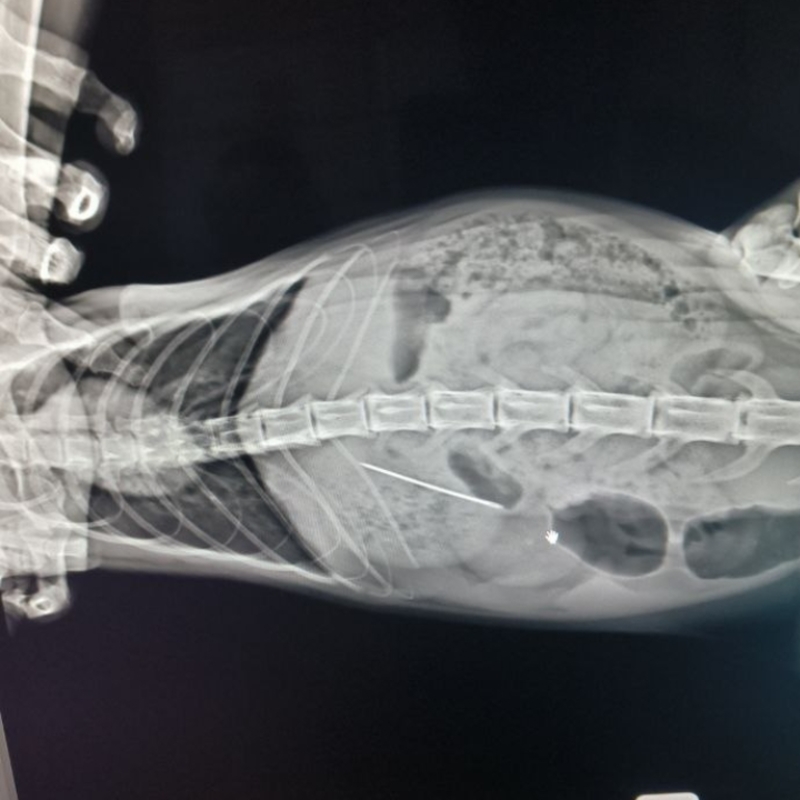

Так и случилось с Василисой: забавляясь с ниткой, она проглотила и ее, и иголку. Срочный выезд в клинику, рентген - и, к счастью, обнаружено, что иголка находится в желудке, а это значит, ее можно попробовать извлечь эндоскопическим способом!

Эндоскопию успешно провели ветеринарные врачи Клиники БАРС на пр. Чайковского, 23, Анна Владимировна Дроздова и Александра Васильевна Белянина.